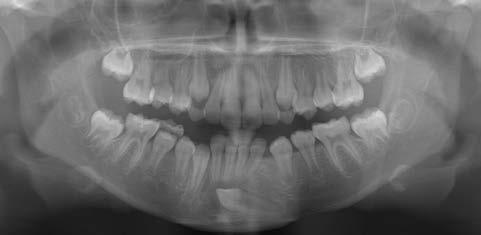

Klinisches Fallbeispiel

Die Panoramaaufnahme zeigt einen horizontal impaktierten Eckzahn im linken Unterkiefer. Eine weitere Untersuchung einer 3D-Aufnahme ergibt einen Zusammenhang zwischen dem impaktierten Zahn und den vorderen unteren Schneidezähnen. Ferner lässt sich ein Zahnsäckchen erkennen, was auf eine vorhandene Dentitionszyste hindeutet.